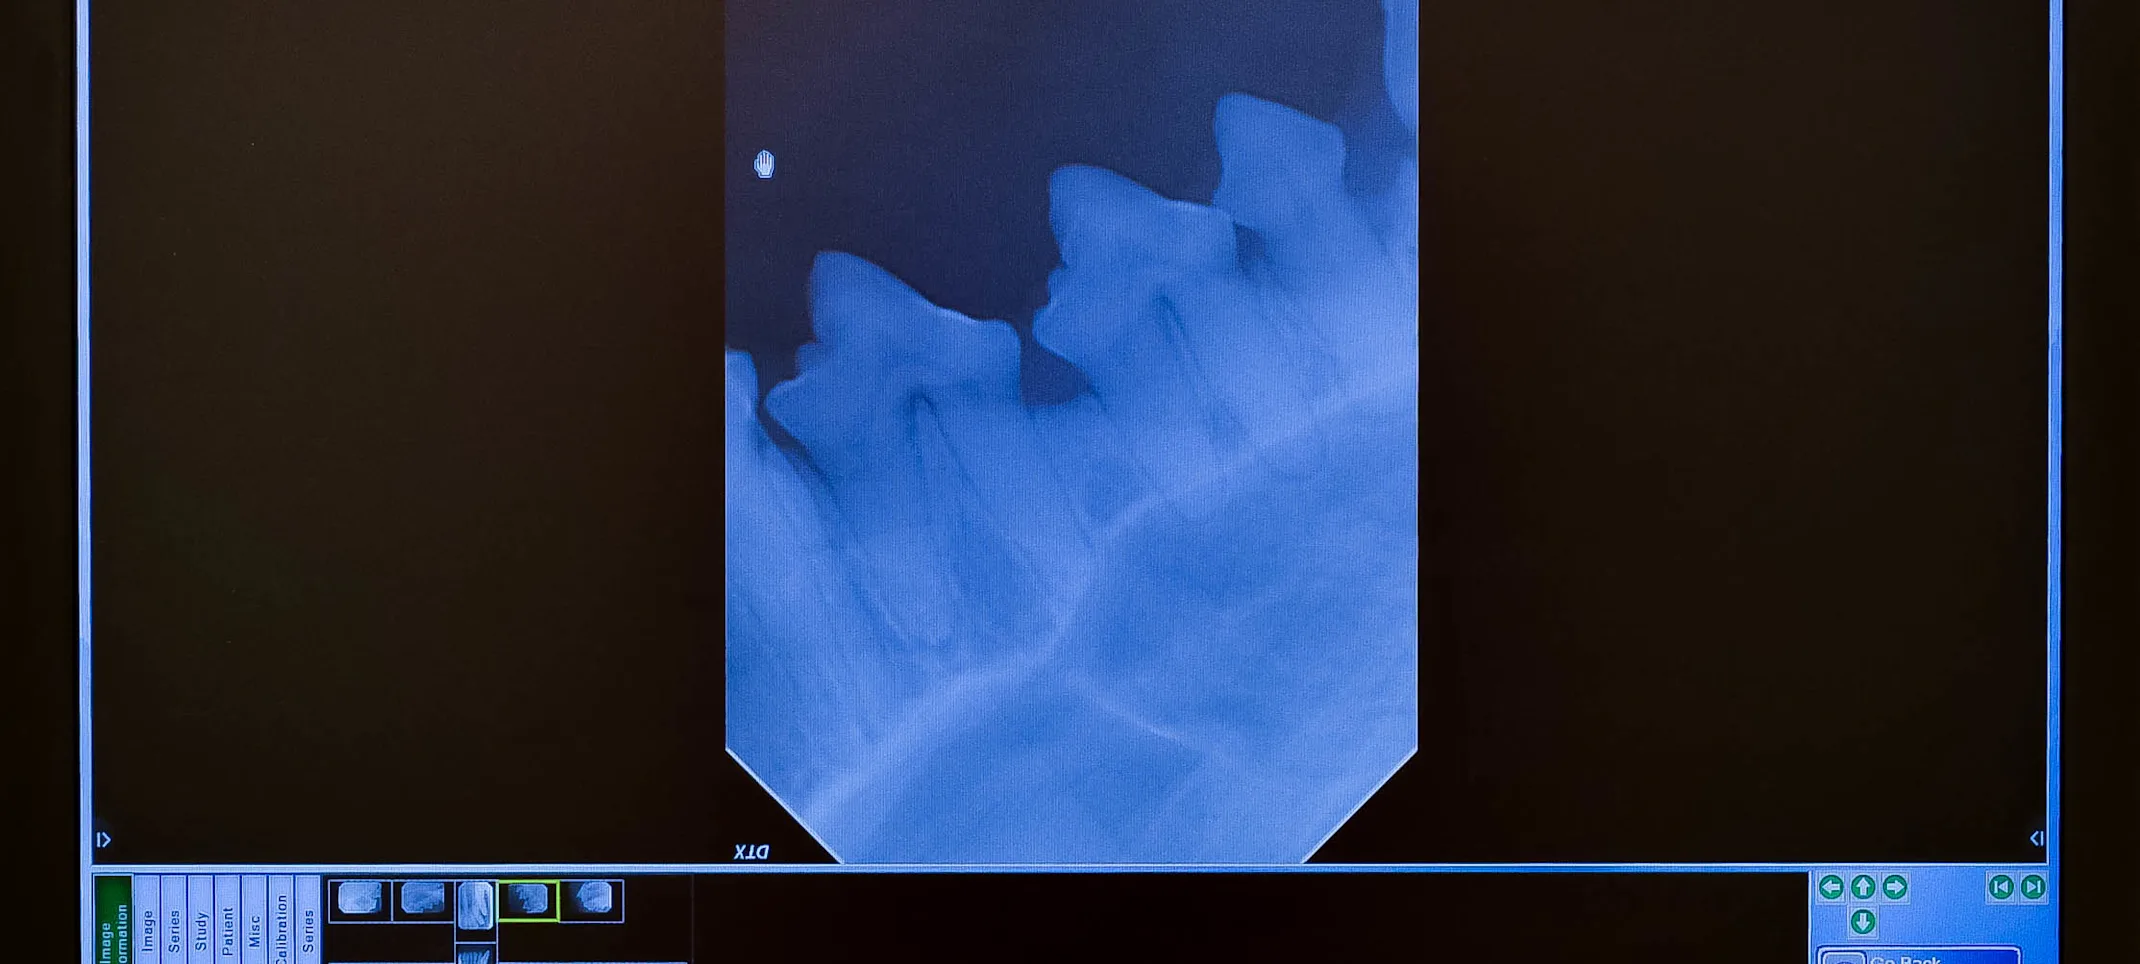

Also similar to human dentistry, we do full mouth radiographs (x-rays) of your pet. This allows our veterinarians to be able to evaluate the roots of your pet's teeth as well as any disease or abnormalities that are located below the gum line and not visible on examination alone.